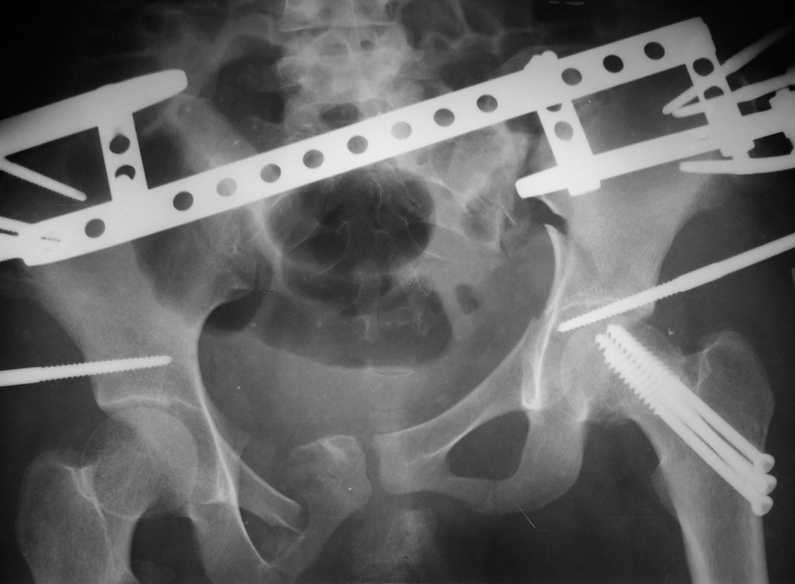

Если говорить о предложенной тактике, то вначале эндопротезирование. Истинное укорочение не большое, около 1-1,5см. Остальное кажущееся за счет приводящей контрактуры. Поскольку пациентка молодая предпочтительно циркониевая (розовая)керамика. Может быть еще укорочение за счет неправильно сросшегося перелома костей таза. На рентгенограммах это не совсем понятно. С уважением. И.Пивень

Привет всем. Укорочение за счет таза не менее 3см.

В задних отделах таза ничего не изменилось (см снимок в аппарате). Картинка кажется лучше за счет оссификата в седалищной вырезке от задней колонны к кп сочленению.

Представленный случай - перелом таза типа С сросшийся со смещением. Укорочение будет не менее 4 см ( Р- гр в краниальной проекции покажет это). Начинать надо с таза.

По первым снимкам имеется сложная травма с переломом ацетабулума (видна линия перелома в задней колонне) и таза с ипсилатеральным переломом шейки. Не удалось репонировать крестцово-подвздошное сочленение, и смещение с ротацией осталось, особенно в верхней ветви лонной кости. Клинические снимки подтверждают остаточную деформацию и укорочение конечности за счет таза.